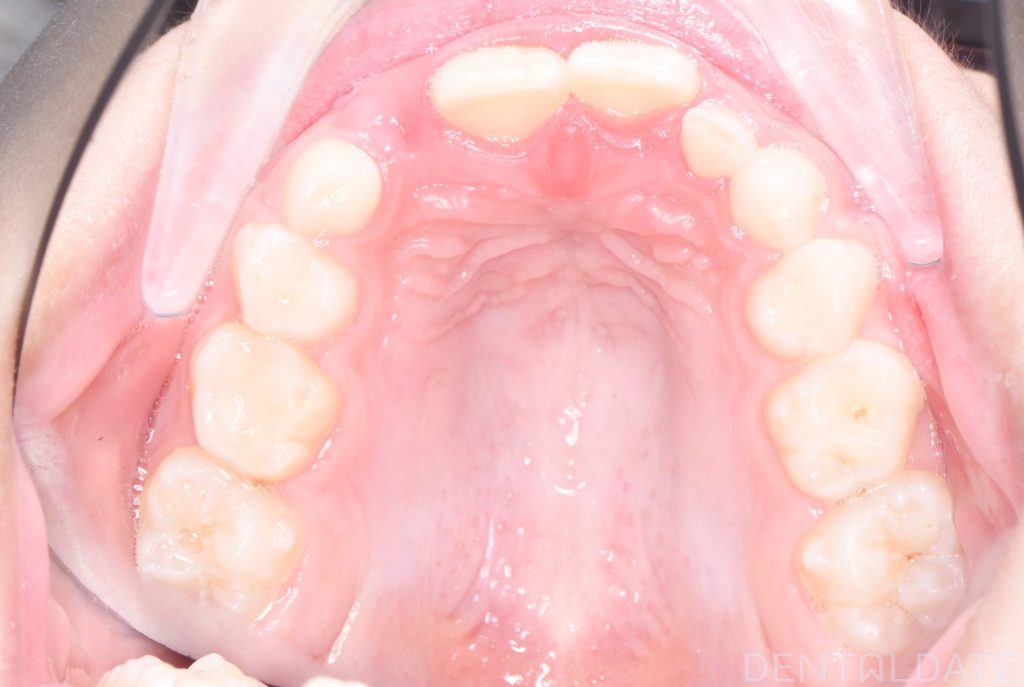

Parents sought an orthodontic consultation due to concerns about the aesthetics of their child’s smile.

To achieve harmony between function and aesthetics, a Haas appliance was used, followed by a myofunctional appliance.